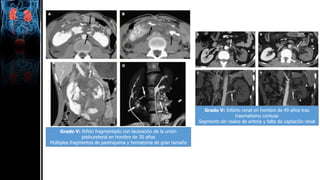

Grado V: Riñón fragmentado con laceración de la unión

pieloureteral en hombre de 30 años

Múltiples fragmentos de parénquima y hematoma de gran tamaño

Grado V: Infarto renal en hombre de 49 años tras

traumatismo contuso

Segmento sin realce de arteria y falta de captación renal